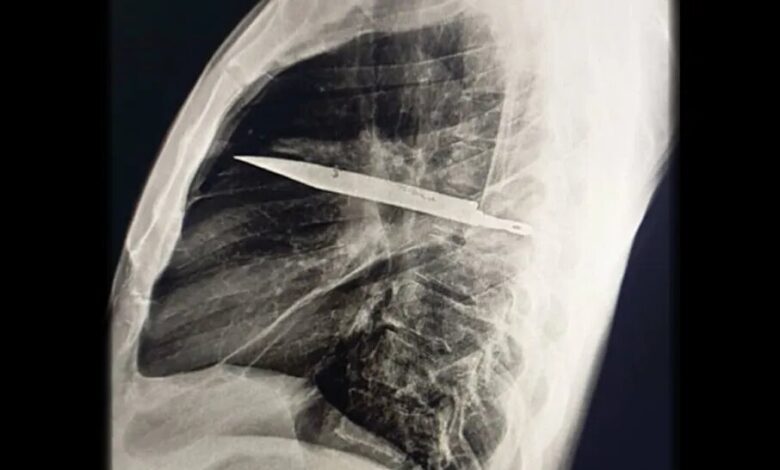

کشف عجیب در قفسه سینه؛ چاقویی که ۸ سال در بدن مردی جا خوش کرده بود/ عکس

تصویربرداری با اشعه ایکس و سیتیاسکن نشان داد تیغهای بزرگ از چاقو از پشت قفسه سینه وارد شده، بین دندههای پنجم و ششم گیر کرده و نوک آن تا جلوی قفسه سینه بین دندههای سوم و چهارم امتداد یافته است. شکستگیهای ترمیمشده در استخوان کتف و چند دنده نیز مشاهده شد. همچنین اطراف تیغه، بافت مرده و چرک تجمع یافته بود.